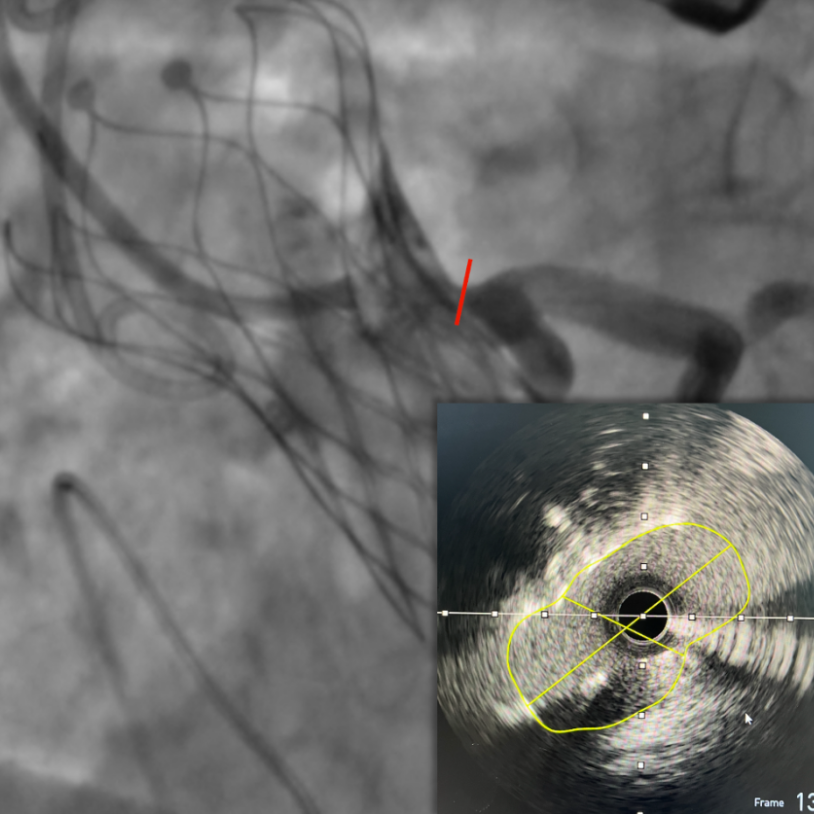

左冠口疑似遮挡

IVUS检查冠脉开口,

进一步精准评估冠脉开口遮挡情况

图片

IVUS检查提示因原瓣叶遮挡,左冠开口受阻,最窄处残余缝隙0.66-0.82mm。

右冠开口残余1.56mm-3.46mm,血流无明显阻挡。